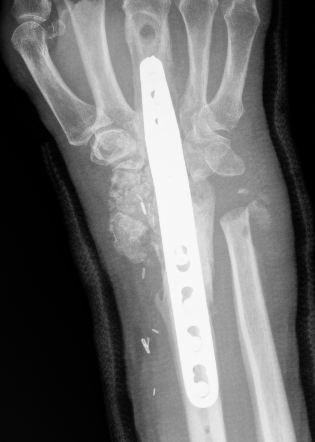

Undisplaced wrist fracture

- interrupts blood supply at a watershed area

- between 3 weeks and 3 months post injry